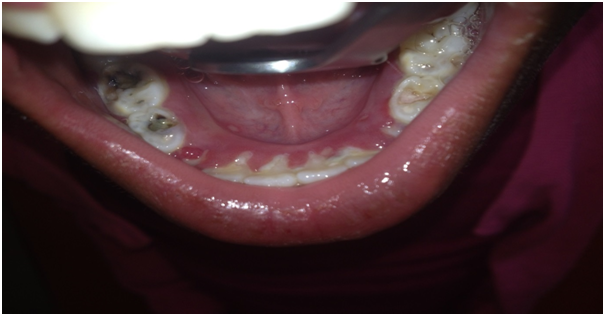

A nine year old, female presented with a main complaint of difficulty eating due to pain associated with multiple shallow oval oral ulcers. The patient’s mother said her daughter complained of pain 3 days ago and she started eating less due to pain and a gradual lack of appetite. She experienced constant pain in the entire mouth without any burning sensation. The pain became more pronounced when she was eating and had difficulty swallowing. On extra oral examination enlarged submandibular lymph nodes were palpable both on left and right side which were mobile, tender and soft in consistency. Patient appeared weak and dehydrated and had a fever. Her speech was slurred and she had no known allergies and she was HIV negative. On intra oral examination she had an erythematous area surrounding the inner border of the upper and the lower labial mucosa (Figure 1). The marginal and attached gingiva was swollen and inflamed, the gingiva formed tissue tags over the lower primary canines (73 and 83) characterized by erythema, oedema, capillary proliferation (Figure 2). Multiple shallow ulcers measuring less than 0.5cm were present on the floor of the mouth, tongue lateral borders, the buccal, labial and gingival mucosa which were surrounded by an erythematous area (Figures 3 & 4). Patient had no oozing from any of the ulcers however they were extremely painful on swallowing or talking. The patient had severe halitosis and a high salivary flow and her teeth had a severe build-up of in plaque and calculus deposits. The lower posterior molars (74, 75, 84 and 85) had tooth decay however the teeth were asymptomatic.

Figure 2: Inflammation of the marginal and attached gingivae.

Figure 4: Multiple ulcers on lower gingival mucosa and floor of the mouth.